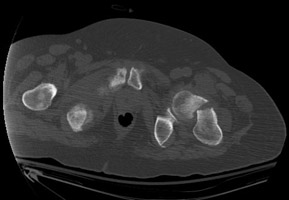

- Click on the image for a larger versionEAxial CT. This image clearly demonstrates the pathologic fracture through the left femoral neck at the location of a sclerotic bone metastasis.